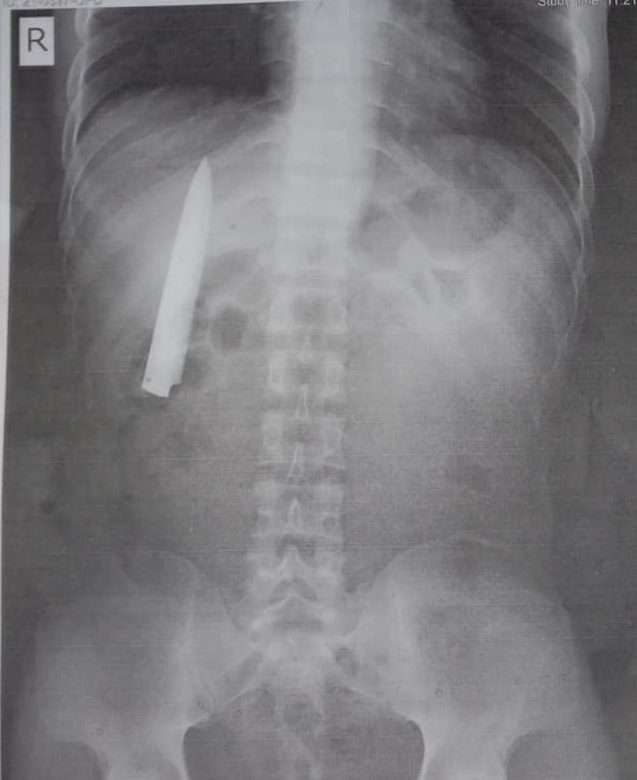

Kent Dan Hasil Rontgen Dadanya (Foto: Worldofbuzz.com)

Seperti kasus yang dialami seorang pria berusia 25 tahun dari Filipina. Menurut The Inquirer, pria bernama Kent Ryan Tomao ini baru sadar ada pisau tertanam di dadanya setelah melakukan rontgen yang akan digunakan untuk keperluan melamar pekerjaan di sebuah perusahaan pertambangan yang ada di Agusan del Sur.

Namun, hal ini berbeda dengan Kent yang memiliki pisau di dalam tubuh dan hal tersebut tidak diketahuinya. Ia baru tahu setelah dokter memberitahukannya bahwa ada benda yang menyerupai pisau bersarang sekitar beberapa inci dari paru-paru. Kent pun bingung dengan kondisi tersebut.

Keberadaan pisau di dalam tubuh Kent ternyata menyimpan cerita masa lalu, tepatnya pada 4 Januari 2020. Di mana ia pernah mengalami luka akibat ditusuk oleh beberapa remaja saat pulang kerja. Ketika itu kondisi Kent juga hampir tidak terselamatkan.